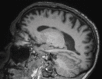

Neurodegenerative diseases are a devastating group of disorders that can be difficult to accurately diagnose. Although these disorders are difficult to manage owing to relatively limited treatment options, an early and correct diagnosis can help with managing symptoms and coping with the later stages of these disease processes. Both anatomic structural imaging and physiologic molecular imaging have evolved to a state in which these neurodegenerative processes can be identified relatively early with high accuracy. To determine the underlying disease, the radiologist should understand the different distributions and pathophysiologic processes involved. High-spatial-resolution MRI allows detection of subtle morphologic changes, as well as potential complications and alternate diagnoses, while molecular imaging allows visualization of altered function or abnormal increased or decreased concentration of disease-specific markers. These methodologies are complementary. Appropriate workup and interpretation of diagnostic studies require an integrated, multimodality, multidisciplinary approach. This article reviews the protocols and findings at MRI and nuclear medicine imaging, including with the use of flurodeoxyglucose, amyloid tracers, and dopaminergic transporter imaging (ioflupane). The pathophysiology of some of the major neurodegenerative processes and their clinical presentations are also reviewed; this information is critical to understand how these imaging modalities work, and it aids in the integration of clinical data to help synthesize a final diagnosis. Radiologists and nuclear medicine physicians aiming to include the evaluation of neurodegenerative diseases in their practice should be aware of and familiar with the multiple imaging modalities available and how using these modalities is essential in the multidisciplinary management of patients with neurodegenerative diseases.©RSNA, 2020.